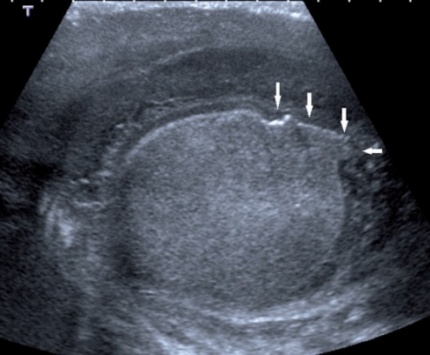

- Bất thường đường viền tinh hoàn: khi tinh hoàn vỡ, sự đùn ra của nhu mô tinh hoàn qua chỗ vỡ sẽ tạo nên sự di thường của một bề mặt tinh hoàn bắng phẳng bình thường (Hình5).. Khi có khối máu tụ lớn ngoài tinh hoàn hay khối máu tụ lớn ở vùng bìu làm khó phát hiện dấu hiệu rách bao trắng tinh hoàn thì hình ảnh này là dấu hiệu gián tiếp của vỡ tinh hoàn

Hình 5. Bất thường đường viền tinh hoàn* Nguồn: theo Adlan T (2014) [1]